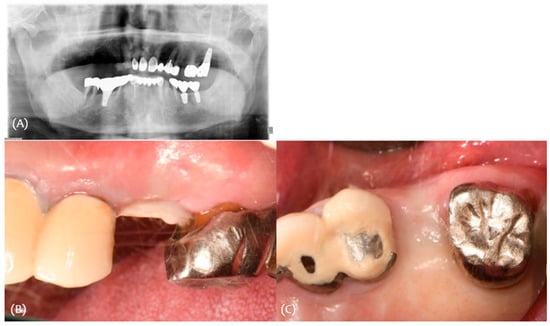

3.2. Case 2

2.2. Surgical Protocol